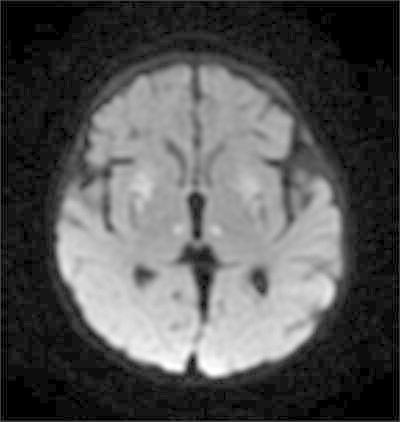

The patient had been doing well until 4 months of age, when he was noted to be losing weight by his primary care provider. He was admitted for an evaluation of failure to thrive and hypotonia. A brain MRI and an EEG were obtained for a concern for seizure-like activities. The EEG was initially normal. A brain MRI revealed abnormal signal and restricted diffusion in bilateral lenticular nuclei, the medial thalami and the caudate nuclei, as well as encephalomalacia (Figs. 1 and 2). An MR spectroscopy showed a lactate peak in the left anterior basal ganglia (Fig. 3). These findings were concerning for an underlying mitochondrial disorder, although a hypoxic-ischemic event was also a possibility. A muscle biopsy showed nonspecific changes in SDH, COX, and NADH stains. Electron transport chain enzyme spectrophotometry assay on snap frozen quadriceps muscle was unremarkable except for a reduced enzyme activity of the complex II (31% of mean). Respiratory chain complex V (ATP synthase) activity was not measured due to a technical limitation. A mitochondrial DNA mutation screening panel (leukocytes) was ordered due to the MRI findings and revealed homoplasmic m.8993T>G mutations in the MT-ATP6 gene encoding ATP synthase, leading to the diagnosis of Leigh syndrome. The mutant load was confirmed by real-time allele refractory mutation system (ARMS) quantitative PCR analysis. Mild persistent lactic acidosis with lactate levels in the range of 3–7 mol/L was consistent with the diagnosis. A therapy with coenzyme Q10 was started for the treatment of Leigh syndrome. l-citrulline was restarted at an increased dose of 1.1 g/day (200 mg/kg/day), as serum citrulline level had decreased to 5 μmol/L. An ophthalmologic eye exam revealed bull’s eye maculopathy consistent with the underlying diagnosis (Laird et al. 2006).

Fig. 2.

Diffusion restriction in subganglionic tissues, lenticular nuclei, and medial thalamic nuclei